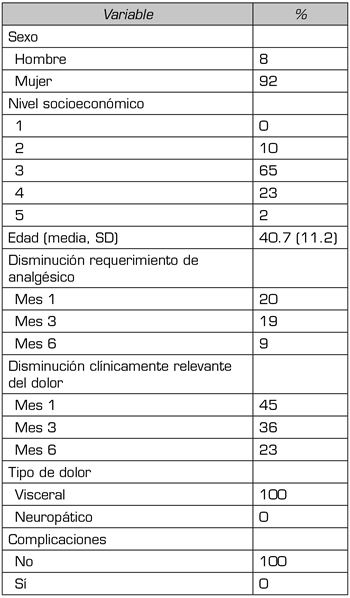

La Tabla 1 presenta las características y resultados individuales de los participantes. El promedio de edad fue 40,6 años (DE ± 11,1), siendo el 92 % mujeres. El 83 % de los pacientes refirieron dolor severo (EVA mayor a 7 puntos) antes de la realización del bloqueo. El porcentaje de pacientes con disminución clínicamente relevante del dolor a los 30 días, a los 3 meses y a los 6 meses del seguimiento fue del 45 %, 36 % y 23 %, respectivamente. El requerimiento analgésico presentó disminución en el 20 % de los pacientes en el primer mes, en el 19 % en el tercer mes y en el 9 % en el sexto mes. No se presentaron complicaciones asociadas al bloqueo.

Tabla I. Características demográficas y clínicas de los participantes (n = 100).

SD: desviación estándar.